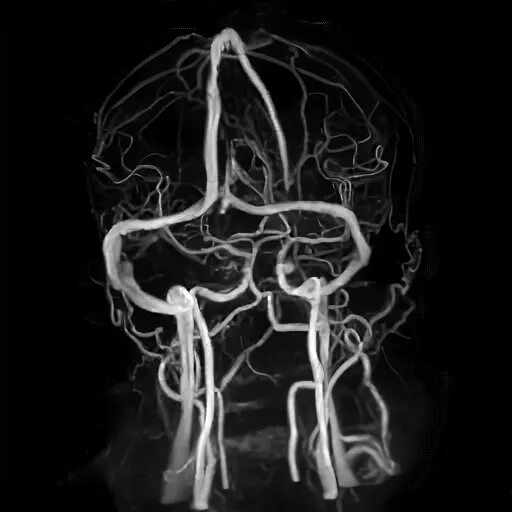

Мрт головного мозга и сосудов тула